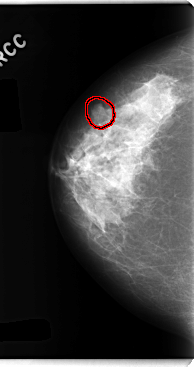

ics_version 1.0 filename C-0234-1 DATE_OF_STUDY 22 12 1994 PATIENT_AGE 40 FILM FILM_TYPE REGULAR DENSITY 2 DATE_DIGITIZED 28 4 1998 DIGITIZER LUMISYS LASER SEQUENCE LEFT_CC LINES 4736 PIXELS_PER_LINE 2240 BITS_PER_PIXEL 12 RESOLUTION 50 NON_OVERLAY LEFT_MLO LINES 4760 PIXELS_PER_LINE 2680 BITS_PER_PIXEL 12 RESOLUTION 50 NON_OVERLAY RIGHT_CC LINES 4760 PIXELS_PER_LINE 2512 BITS_PER_PIXEL 12 RESOLUTION 50 OVERLAY RIGHT_MLO LINES 4688 PIXELS_PER_LINE 2608 BITS_PER_PIXEL 12 RESOLUTION 50 OVERLAY |

FILE: C_0234_1.RIGHT_CC.OVERLAY TOTAL_ABNORMALITIES 1 ABNORMALITY 1 LESION_TYPE MASS SHAPE OVAL MARGINS MICROLOBULATED ASSESSMENT 4 SUBTLETY 5 PATHOLOGY BENIGN TOTAL_OUTLINES 1 BOUNDARY |